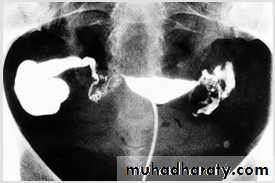

male &female reproductive tractsmammogram

genital tract and mammogram